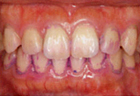

PMTC・歯のクリーニング後